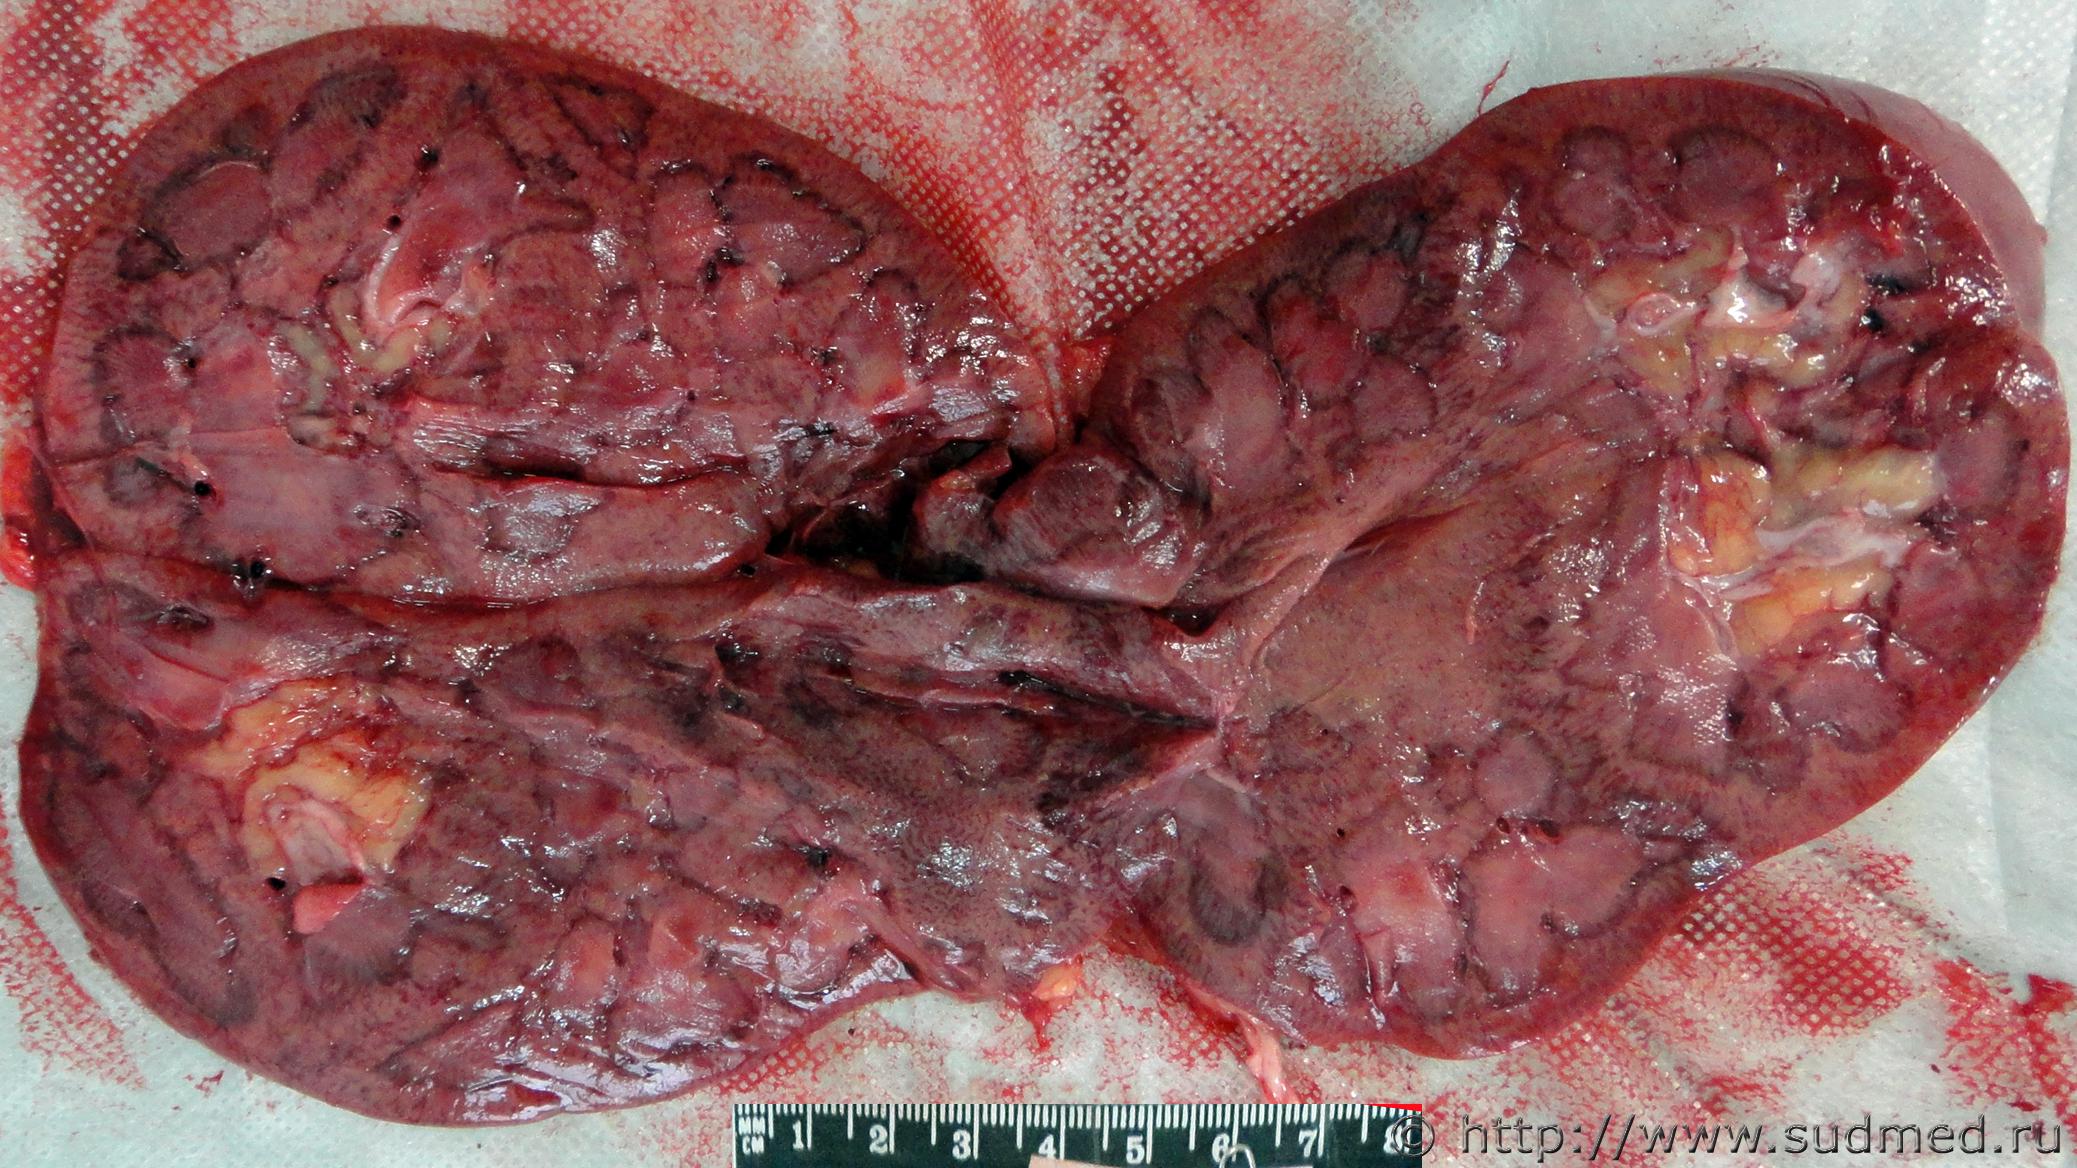

Мужчина, 1967 года рождения.

Обнаружен дома без признаков травмы.

На секции переломы 5-7 го ребер по средней подмышечной линии, 8,9-го ребер на середине между средней подмышечной и задней подмышечной линиями. Разрыв верхнего полюса селезенки. Гемоперитонеум (3 литра)

Мелкоузловой портальный цирроз. Спленомегалия (масса 2 кг, размеры 27х19х11)